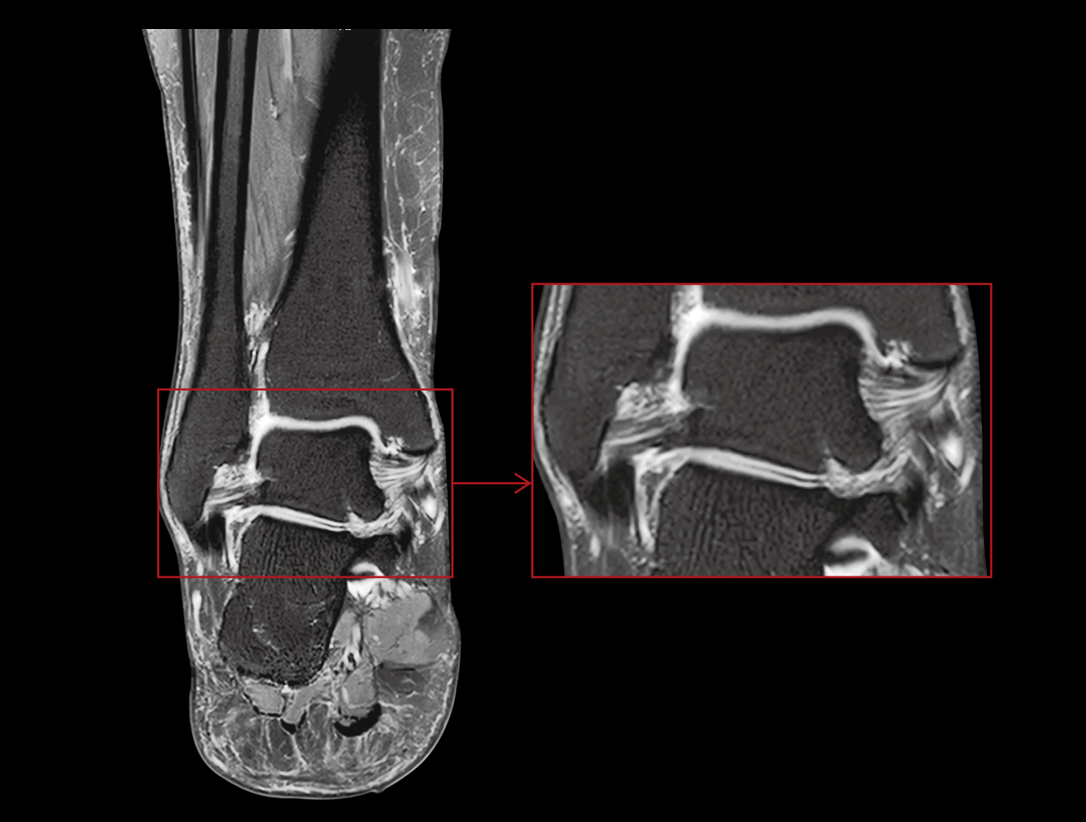

- Media